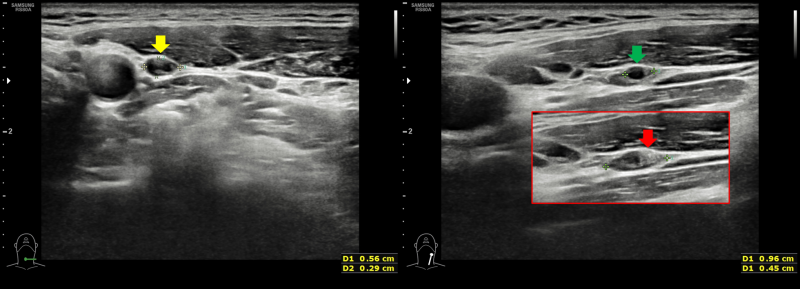

갑상선에 결절이 발견되면 옆 경부 림프절까지 잘 관찰해야 암 진단에도 도움이 되고 수술 범위를 정하는 데도 도움이 됩니다. 그런데 일반적으로 갑상선 암의 진단 환자도 옆 경부 림프절 검사를 게을리하는 일이 많습니다. 다른 병원에서 검사한 뒤 생큐 서울 이비인후과를 찾은 환자(712명)의 초음파 사진을 다시 검토한 결과 66%의 환자의 초음파 검사 사진에서 측 경부 검사가 빠지고 있었습니다.대학 병원 가운데 빅 5도 22%에서 탈락하며 빅 5를 제외한 대학 병원은 48%에서 탈락했어요.샌 환자들을 고마워서울 이비인후과에서 초음파 검사를 했는데, 약 6%의 환자에게서 측 경부 림프절 전이가 발견되었습니다.(해당 내용은 최근 대한 갑상샘 학회에서 발표했습니다.)관련의 증례를 하나 소개합니다.30세 남자 환자가 2년 전으로 건드리는 갑상선 결절에 대해서 상담하기 위해서, 생큐 서울 이비인후과- 내분비 내과 이·운정 원장 외래를 방문했습니다.2017-01-20대학 병원에서 초음파 검사와 총 생검을 실시했습니다만 옆 경부 림프절에 대해서는 전혀 검사를 벌이고 있지 않습니다. 당시 총 생검 결과는 양성 혹(benign follicular nodule이었습니다.*여기서 총 생검이 가는 바늘 흡입 세포 검사보다 항상 좋은 검사가 아님을 알 수 있습니다. (중략)2019-08-03시행한 고마워서울 이비인후과 초음파 사진은 다음과 같습니다.

좌갑상선결절